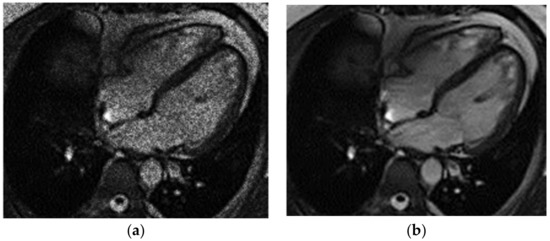

The contour extraction method was used to identify cancerous areas that, after applying the model to eliminate mixed noise, had an increased contrast of volumetric heterogeneous formations in the region of the heart [27]. This method was developed by the authors when analyzing thermal images to assess the condition of the coronary vessels of the myocardium under cardiopulmonary bypass. The contours of the cancerous regions in the examples used for applying the model to eliminate mixed noise (Figure 4, Figure 5, Figure 6, Figure 7, Figure 8 and Figure 9) are highlighted in yellow and they represent the visual boundary of the distribution of volumetric heterogeneous formations.

• For a patient with a history of melanoma: during MRI with contrast enhancement, a volumetric formation adjacent to the atrial septum was visualized in the left atrium (Figure 5).

Figure 5. Heart MRI: (a) image with white noise and (b) denoised image with contrast enhancement of volume melanoma in the left atrium.